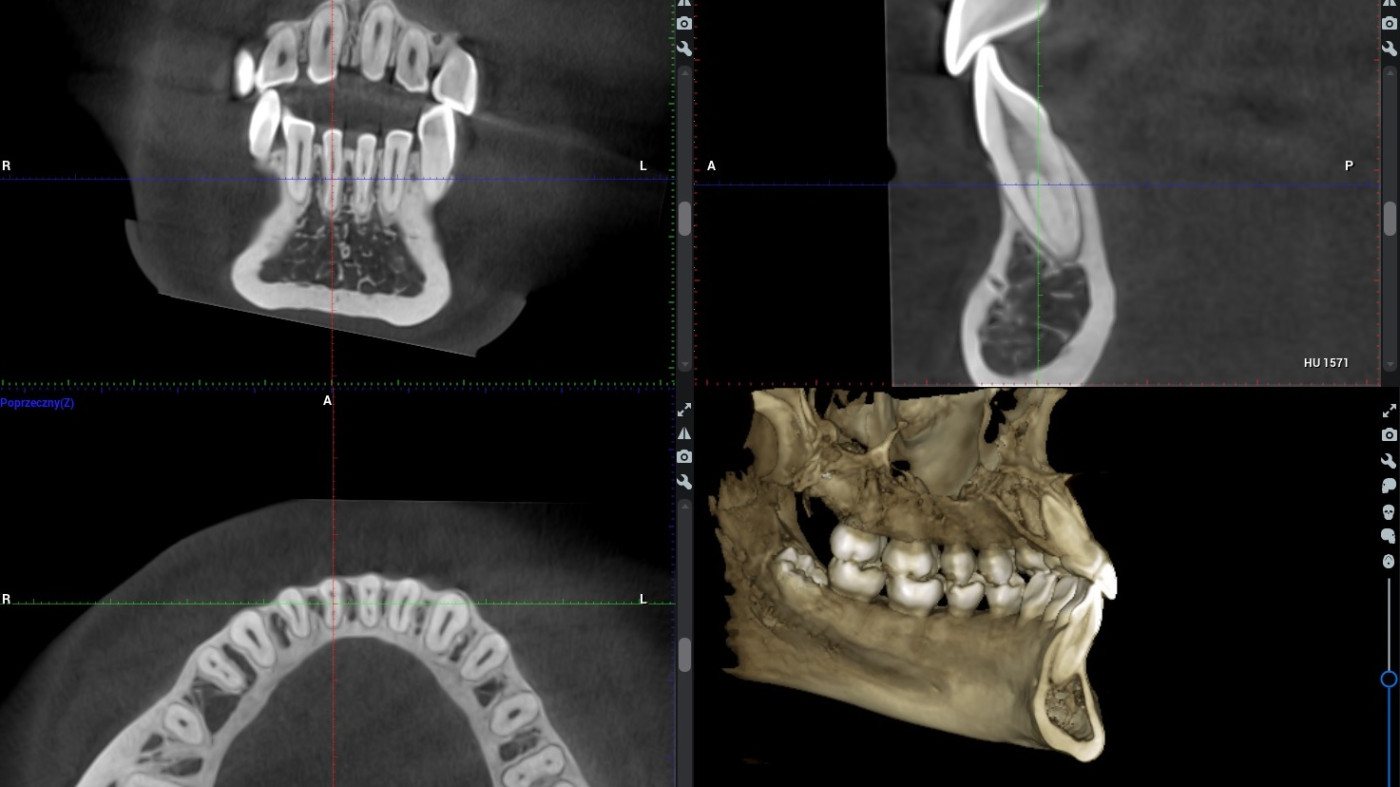

Szkolenie ma na celu przedstawienie możliwości analizy skanów CBCT w przypadku tych oraz innych gałęzi stomatologicznych. Przy wykorzystaniu odpowiednich funkcji w dedykowanym oprogramowaniu możemy zapoznać się z budową anatomiczną zęba leczonego endodontycznie, bądź sprawdzić jakość takiego leczenia, jeśli odbyło się ono w przeszłości.

Możliwa jest precyzyjna ocena położenia zęba zatrzymanego, torbieli, bądź innej zmiany patologicznej w obrębie kości szczęki lub żuchwy. CBCT  pozwala zaplanować wiele zabiegów z zakresu chirurgii (implantacja, ekstrakcje, wyłuszczenie torbieli, etc.) w sposób najbardziej bezpieczny dla pacjenta i wygodny dla lekarza.

Możliwości oraz ograniczenia obrazowania 2D i 3D – kiedy i jakie badanie należy zlecić pamiętając o zasadzie ALARA. Jakość badania RTG – co na nią wpływa, jak ją oceniać, jak wyeliminować potencjalne błędy rzutujące na obniżenie jakości badań radiologicznych. Poruszanie się po badaniu CBCT – możliwości oceny tkanek oraz stanów patologicznych poprzez wyświetlanie badania w formie przekroi, rekonstrukcji wolumetrycznej, rekonstrukcji badań 2D (MPR – multi planar reconstruction). Mnogość narzędzi w oprogramowaniu KaVo RTG – jak efektywnie wykorzystywać je na co dzień w poszczególnych przypadkach z zakresu chirurgii, endodoncji, ortodoncji, etc.

Dokonywanie pomiarów, planowanie położenia wszczepów implantologicznych, lokalizacja kanałów dodatkowych, zębów zatrzymanych oraz inne zagadnienia diagnostyczne spotykane na co dzień w praktyce stomatologa. Podstawy oceny badań RTG w obrębie stomatologii.

Podczas tego praktycznego wydarzenia wspólnie odkryjemy, jak zaawansowane technologie obrazowania rewolucjonizują współcześnie diagnostykę. Razem zgłębimy strategie efektywnego wykorzystania różnych technik diagnostycznych, takich jak tomografia komputerowa i zdjęcia rentgenowskie, w celu precyzyjnej oceny stanu tkanek zęba oraz korzeni. Dokonamy także analizy obrazów i pokażemy, jak dokładne diagnozy mogą wpłynąć na skuteczność leczenia endodontycznego.

• poruszania się po oprogramowaniu dedykowanemu 3D.